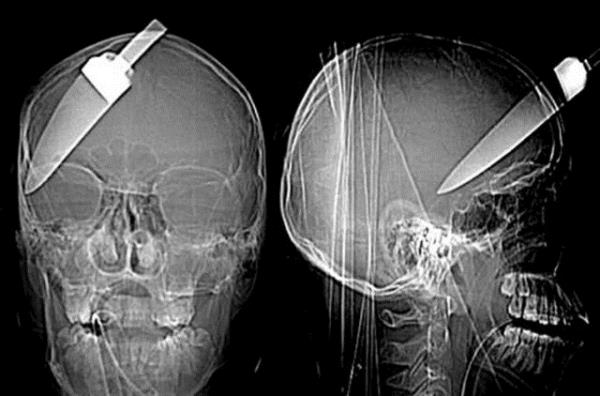

10. Londra'da başına bıçak saplanan 16 yaşındaki bu çocuk bir mucize eseri kurtuldu.

Londra'da başına bıçak saplanan 16 yaşındaki bu çocuk bir mucize eseri kurtuldu.

22. İsidro Mejia adlı Los Angeles'ta yaşayan bir inşaat işçisi geçirdiği kazayla ölümden döndü. Bir anlık dikkatsizlik sonucu makinadan fırlayan tam altı çivi kafatası ve boynuna saplandı.

İsidro Mejia adlı Los Angeles'ta yaşayan bir inşaat işçisi geçirdiği kazayla ölümden döndü. Bir anlık dikkatsizlik sonucu makinadan fırlayan tam altı çivi kafatası ve boynuna saplandı.